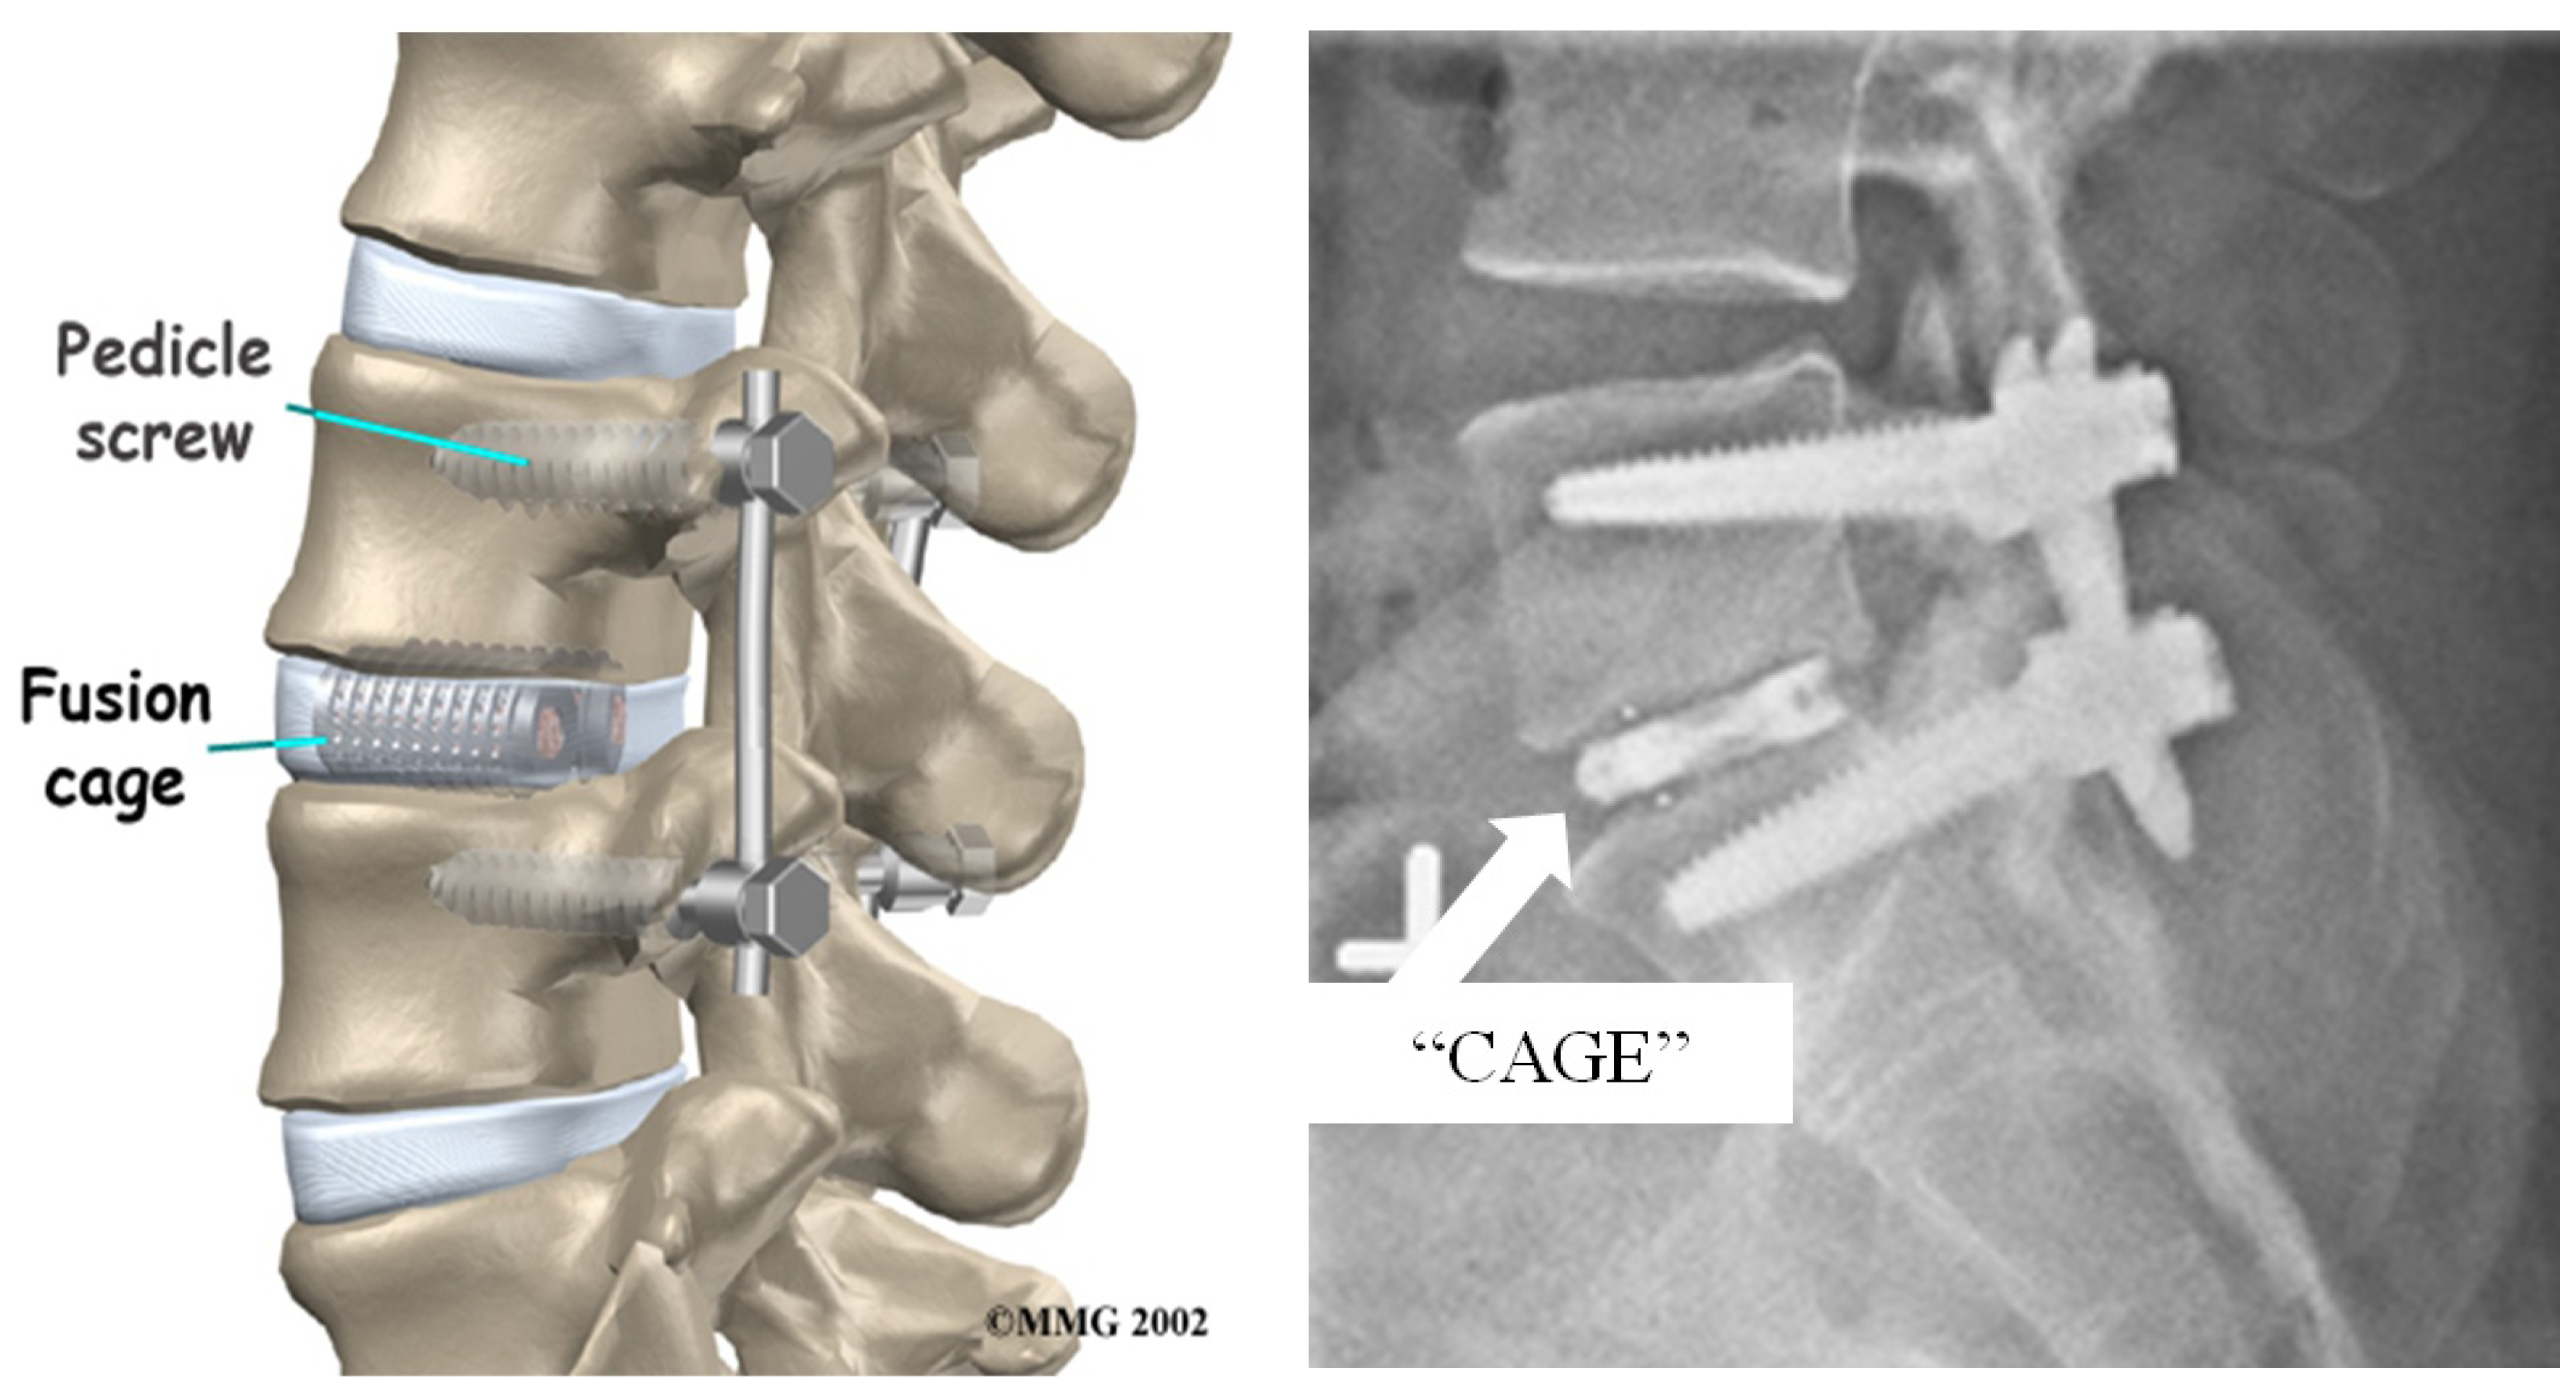

4.2.2. Spinal Fusion Surgery

- Nouh, M.R. Spinal fusion-hardware construct: Basic concepts and imaging review. World J. Radiol. 2012, 4, 193–207. [Google Scholar] [CrossRef] [PubMed]

- Confusion about Spinal Fusion. Available online: https://www.spineuniverse.com/treatments/surgery/lumbar/confusion-about-spinal-fusion (accessed on 22 March 2017).

- Multilevel Spinal Fusion for Low Back Pain. Available online: https://www.spine-health.com/treatment/spinal-fusion/multilevel-spinal-fusion-low-back-pain (accessed on 21 March 2017).